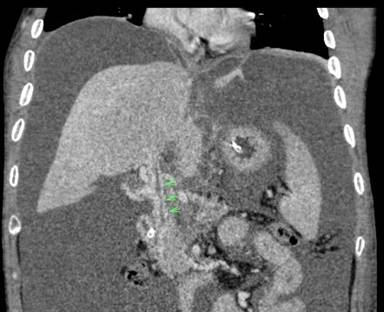

Portal Biliopathy

Collaterals in CTPV can mechanically obstruct the biliary track giving rise to Portal Biliopathy (PB) (Figure 2) [19]. Occurrence of PB in CP is a rare phenomenon [19, 20]. These vessels may cause ischemia induced fibrosis of the track. Majority do not manifest any symptoms of biliary obstruction [16]; chronic cholestasis, biliary pain and calculus may occur in a few. However, symptoms related to portal hypertension are more frequent than symptoms of chronic cholestasis [21]. Rana et al. described endoscopic ultrasonography (EUS) features of PB in a female suffering from acute severe pancreatitis [20]. EUS features include prominent common bile duct with anechoic serpentine veno-venous collaterals around the biliary tree. ERCP however, is the key investigation; although MRCP is equally accurate for diagnosing PB[21]. MRCP with MR portography has the additional advantage of distinguishing bile duct varices from biliary duct calculi. Cholangiographic findings include segmental upstream dilation, caliber irregularity, stricture, extrinsic impression due to collaterals (the pseudocholangiocarcinoma sign) [21]. The strictures are typically smooth unlike those of sclerosing cholangitis [21]. Intervention is required in patients with a dominant biliary stricture and features of obstructive jaundice. In patients with a shuntable vein, a portosystemic shunt is performed or else endotherapy is preferred [21].

|

Figure 2. CECT coronal reformation demonstrates dilated common bile duct (green arrows) surrounded by numerous collaterals in a setting of portal biliopathy. |